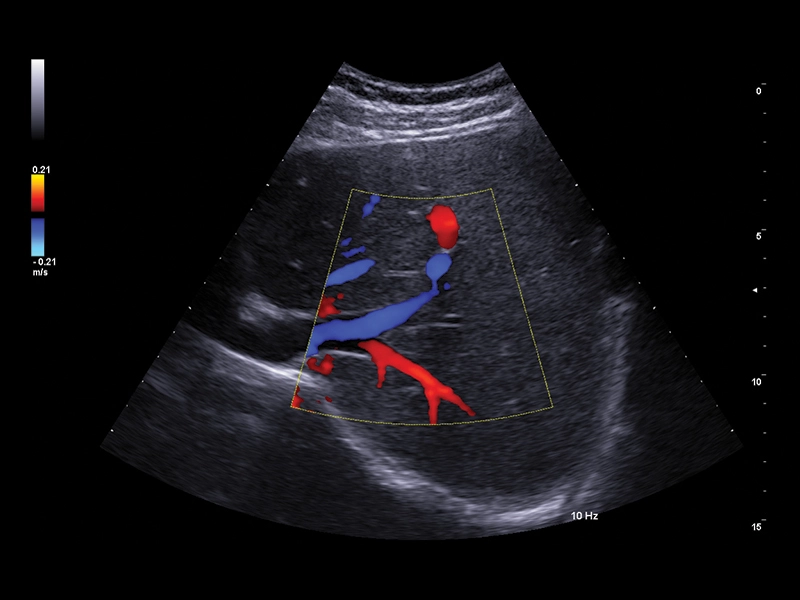

MyLab™C25 - X-FLOW 2

MyLab™C25 - X-FLOW 2